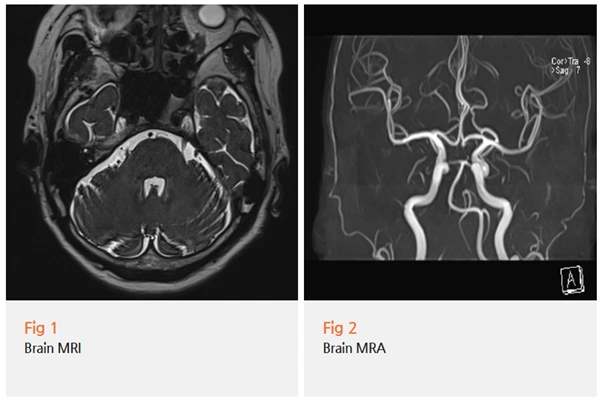

그래서 뇌 MRI, MRA, 그리고 목 엑스레이까지

포괄적인 검사를 진행했습니다.

검사 결과를 보니, 삼차신경통의 가장 흔한 원인인

신경혈관압박은 명확하게 관찰되지 않았어요.

하지만 경추부,

즉 목에 구조적인 문제가 있다는 걸 확인할 수 있었습니다.

"목이 얼굴 통증과 무슨 상관이에요?"

경추부의 구조적 문제는 삼차신경계를 포함한

두경부 통증의 중요한 악화 인자로 작용할 수 있거든요.

특히 목뼈의 정렬이 틀어지거나,

목 근육이 경직되면 신경이 자극을 받아

얼굴 쪽 통증이 더 심해질 수 있습니다.